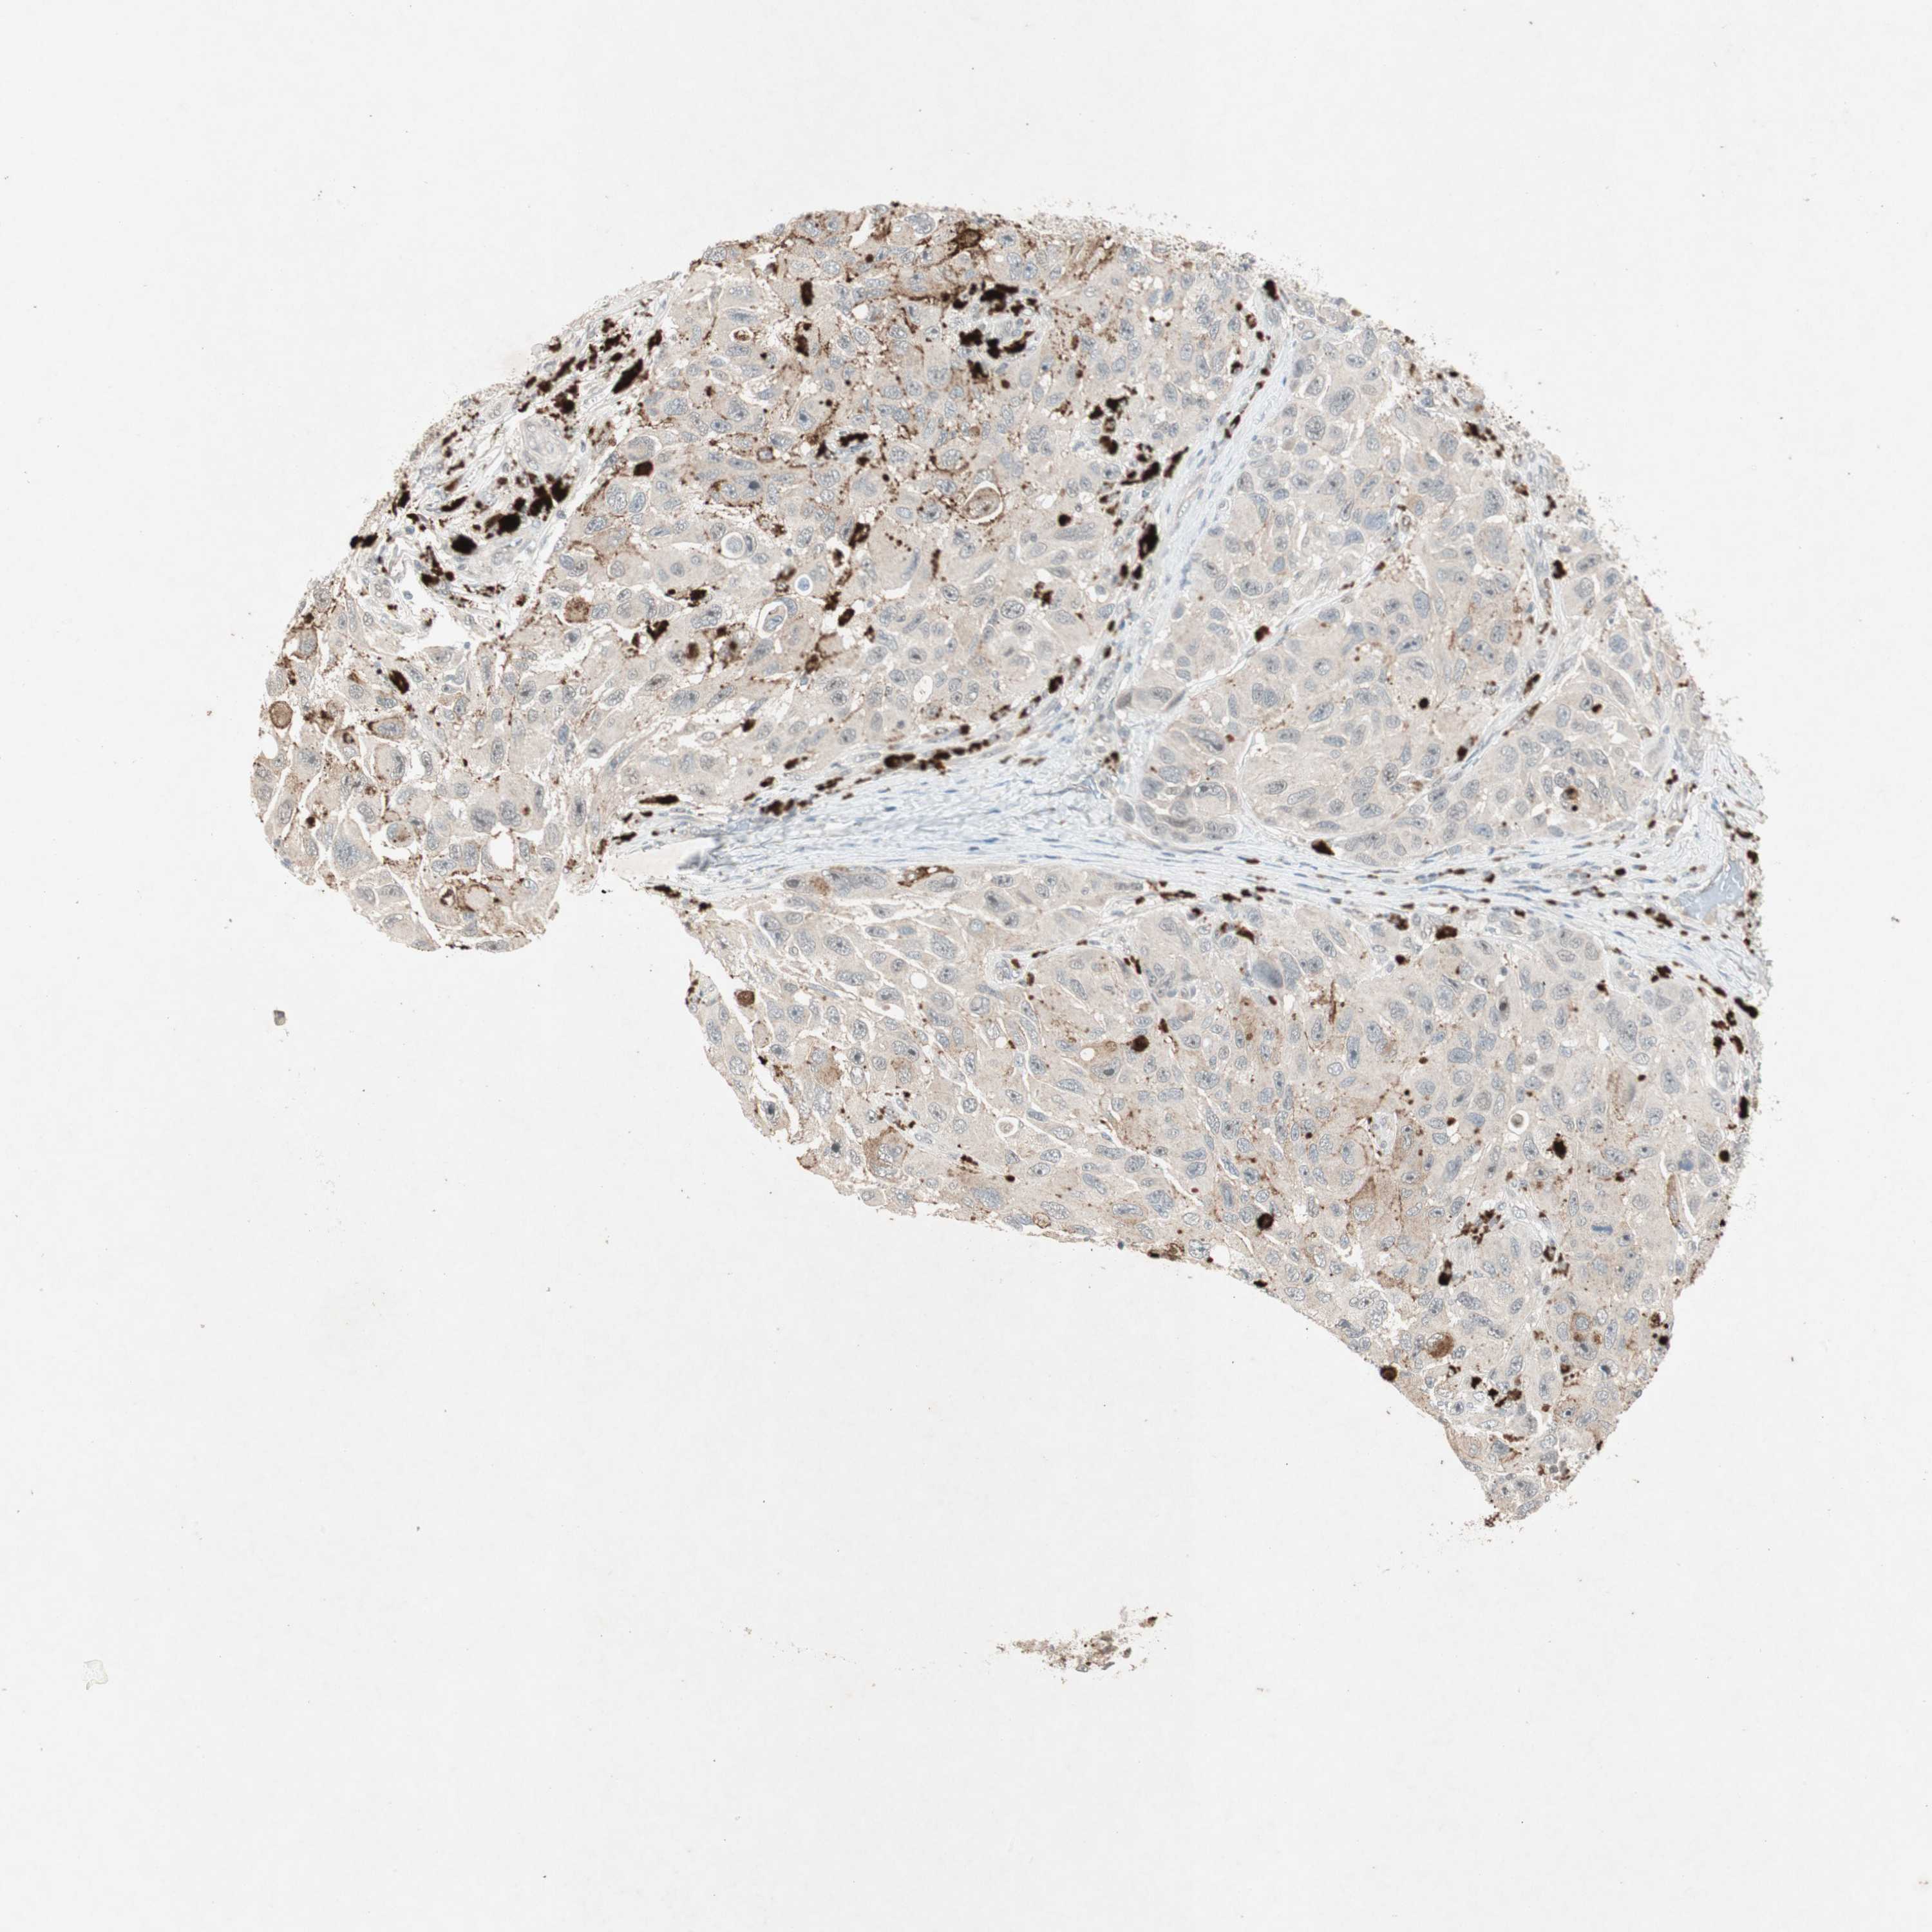

MELANOMA - Protein expressioni

A mouse-over function shows sample information and annotation data. Click on an image to view it in a full screen mode. Samples can be filtered based on level of antibody staining by selecting one or several of the following categories: high, medium, low and not detected. The assay and annotation is described here.

Note that samples used for immunohistochemistry by the Human Protein Atlas do not correspond to samples in the TCGA dataset.

Antibody stainingi

Antibody staining in the annotated cell types in the current human tissue is reported as not detected, low, medium, or high, based on conventional immunohistochemistry profiling in selected tissues. This score is based on the combination of the staining intensity and fraction of stained cells.

Each image is clickable and will lead to virtual microscopy that enables deeper exploration of all samples and also displays staining intensity scores, fraction scores and subcellular localization as well as patient and tissue information for each sample.

Antibody HPA003750

Staining

High

Medium

Low

Not detected

Intensity

Strong

Moderate

Weak

Negative

Quantity

>75%

75%-25%

<25%

None

Location

Nuclear

Cytoplasmic/membranous

Cytoplasmic/membranous,nuclear

Malignant melanoma, NOS

Malignant melanoma, Metastatic site